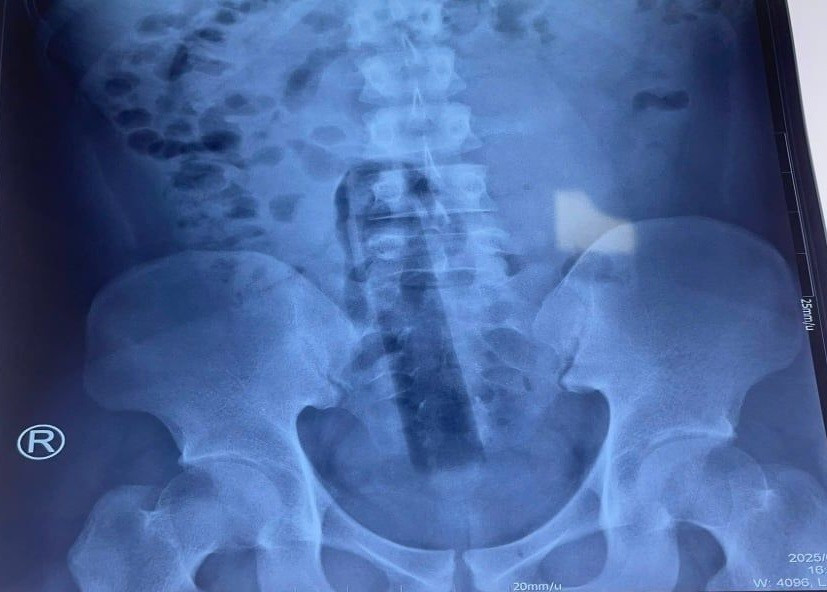

Hình ảnh X-quang cho thấy dị vật nằm sâu trong khung chậu. BS.CKII Đặng Khải Toàn – Phó Trưởng khoa Ngoại Tổng hợp, cho biết: “Do đoạn cán cây lau nhà không có điểm chặn bên ngoài và không phải vật dụng chuyên dụng cho cơ thể người, nó đã mắc kẹt tại vị trí sâu, gây đau và nguy cơ biến chứng cao. Việc lấy dị vật ra không thể thực hiện bằng phương pháp thông thường hoặc nội soi qua ngả hậu môn”.

Dị vật được các bác sĩ xác định đã trôi sâu vào trực tràng của người bệnh